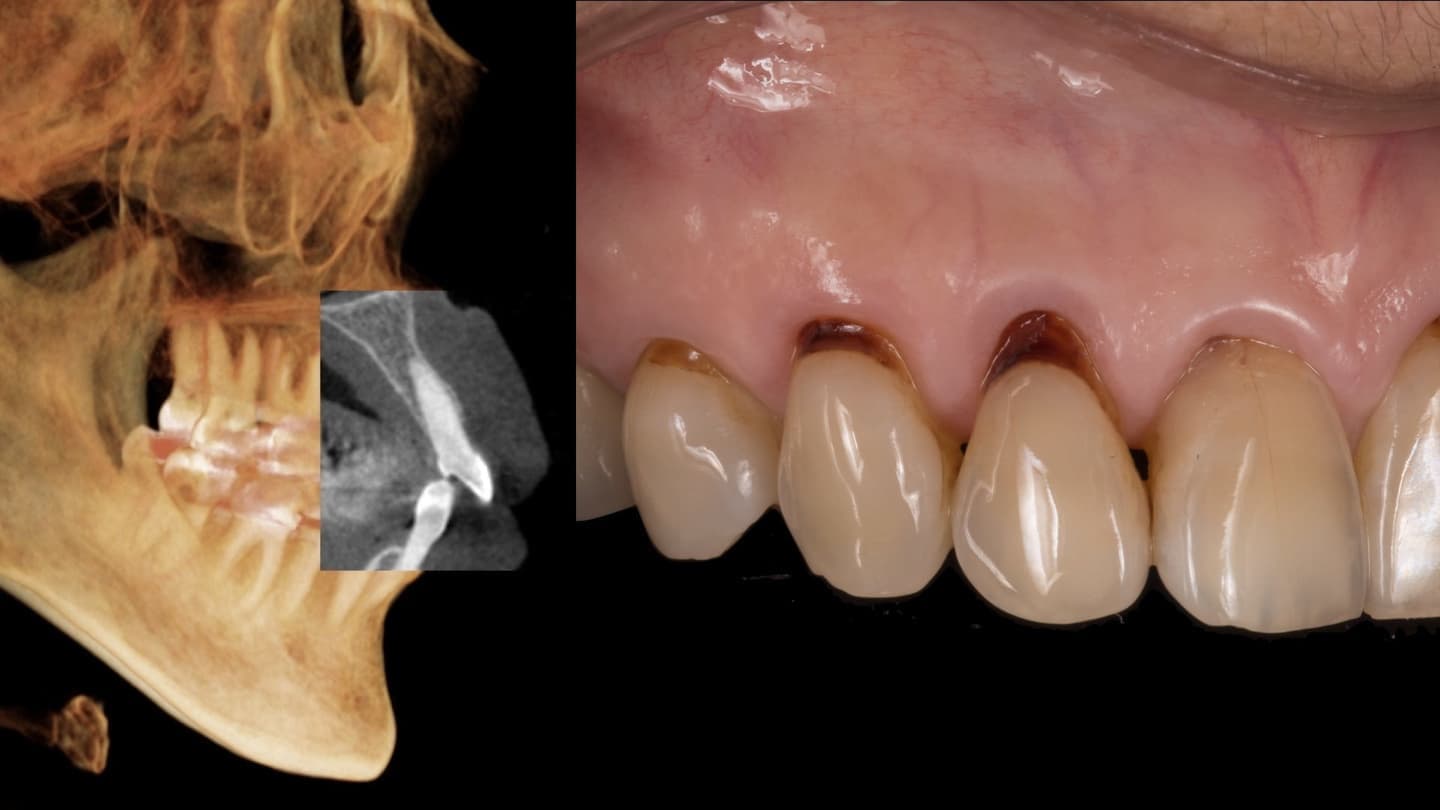

基本的な検査だけでなく、CT検査、歯周病に特異的な細菌のPCR検査、噛み合わせの検査、生活習慣の見直しなどを行います

他院では見逃してしまうケースもしっかり対応します

専門医ではないと対応できない症例もあります